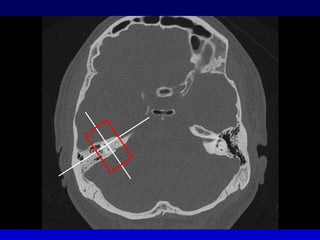

PöschlPlano en 45° oblicuo al plano coronal y sagitalSecciona el peñasco en el plano perpendicular a su ejeEl CSS aparece como un anillo con un arco entero de su pared superiorSe traza paralelo al curso del CSS

PÖSCHL

Proyección de StenverPerpendicular al plano de PöschlTambién es en 45° oblicuo al plano coronal y sagital, pero rotado en 90° Muestra las vueltas de la cóclea y  en  sección de corte la cortical superior del CSS

STENVERSTENVER